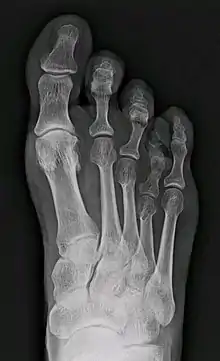

Брахиметатарзи́я (англ. brachymetatarsia, др.-греч. βραχυμεταταρσια: βραχυ — короткий; μεταταρσιο — плюсна) — это возникающая вследствие неизвестных причин редкая аномалия развития (укорочение) одной или нескольких плюсневых костей. Преждевременное закрытие зоны эпифизарного роста приводит к появлению дефекта: палец стопы (чаще всего четвёртый, но может быть и любой другой)[1], длина которого не изменена, располагается несколько проксимальнее и выше остальных. Брахиметатарзия может быть одно- или двусторонней, с преобладанием последней (72% случаев)[1]. Если затронуто более одного пальца на одной ноге, то такой порок называется брахиметаподией[2]. Укорочение первой плюсневой кости вызывает состояние, известное как палец Мортона, которое, впрочем, рассматривается как вариант нормы, поскольку не приводит к существенным изменениям внешнего вида стопы и появлению жалоб.